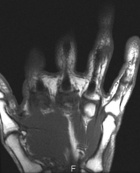

64 year old female presents with c/o persistent vs recurrent mass in her L ring finger. She recently had an excisional biopsy performed by another surgeon, who was performing a first dorsal compartment release on her as well. NVI

Zoom image: Radiological image Radiological image.